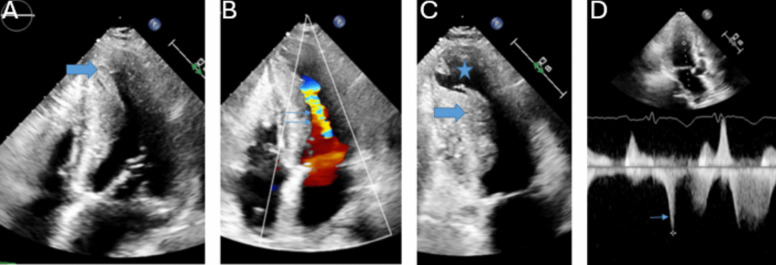

Purpose of review: The purpose of this review is to highlight the utility of echocardiography in the diagnosis and management of cardiomyopathies.

Recent findings: Echocardiographic parameters function synergistically to guide decision-making ranging from early detection of disease and screening to risk stratification of complex disease. The collective wealth of information available from 2D/3D assessment, Doppler, diastology and strain makes echocardiography an invaluable decision aid.